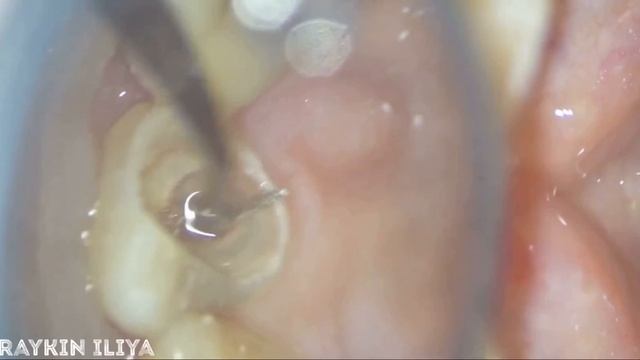

Извлечение инструмента из канала зуба , лечение зубов , пломбировка зубов , отбеливание зубов,винир смотреть онлайн

01:12

Извлечение инструмента из канала зуба , лечение зубов , пломбировка зубов , отбеливание зубов,винир

Уборка с осознанным подходом 18 просмотров